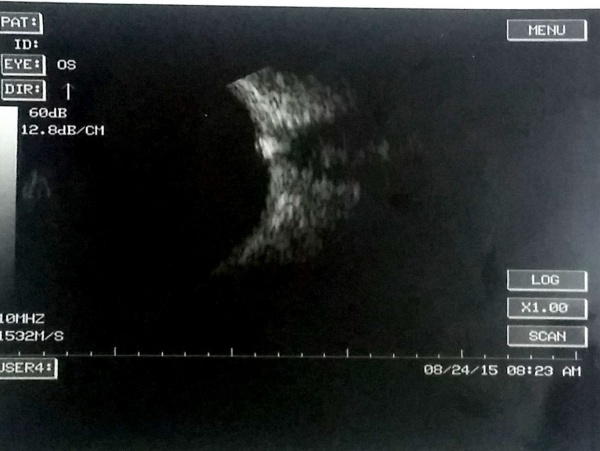

Ultrasonographic features of retinal detachment versus posterior vitreous detachment

One of the most important use of ocular ultrasound is to rule out a retinal detachment (RD) which may require vitreoretinal surgical intervention. Differentiation of a posterior vitreous detachment (PVD) from RD is important. An old RD may also have retinal macrocysts[4] at the macula or retinal periphery, which is detectable by the ultrasonography.

The retinal shortening and retinal to choroidal length ratio may denote an increased risk for recurrent retinal redetachment after vitreoretinal surgery.[5] Ocular echography may detect the location of break and characteristic of break (e.g., giant retinal tear). The amplitude of subretinal echoes may give a clue to its nature (clear fluid is anechoic; hemorrhage and turbid proteinaceous fluid show point echoes of mild to moderate amplitude).